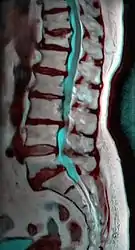

MRI of L5-S1 anterolisthesis

Anterolisthesis L5/S1